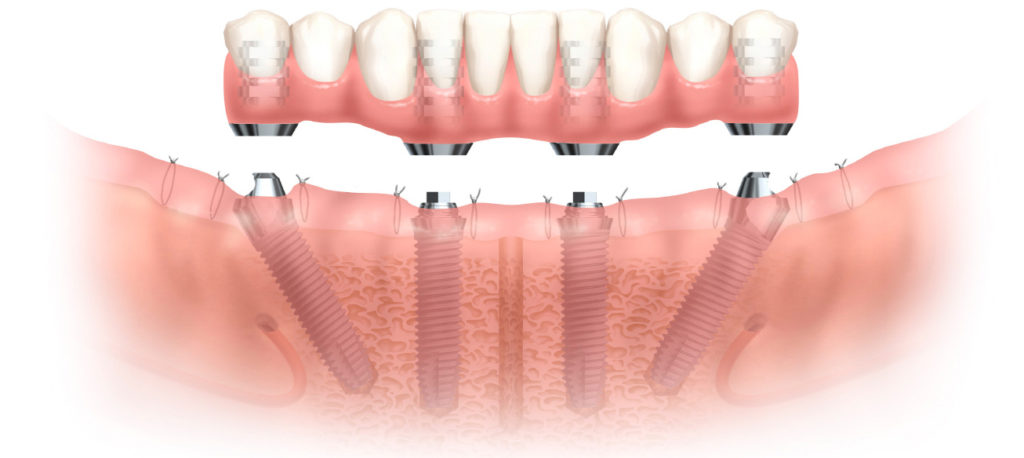

ALL-ON-4® Implants

The ALL-ON-4® technology is currently the most modern procedure in the field of implantology. The expression itself refers to all teeth being supported on four dental implants, per jawbone. This innovative technique provides a great solution for people with more missing teeth, even in case of complete toothlessness, to completely secure both upper and lower jaw area.

One of the biggest advantages of this technique is that the dentures are affixed to the implants at a special angle, which means that the implantation can be performed without sinus elevation or bone replacement surgery. Moreover, the extraction of remaining teeth, the implantation itself and the insertion of temporary bridge are all carried out in one session.

All of these factors contribute to reduced healing time, optimised overall cost, gaining confidence and comfort in a shorter amount of time.